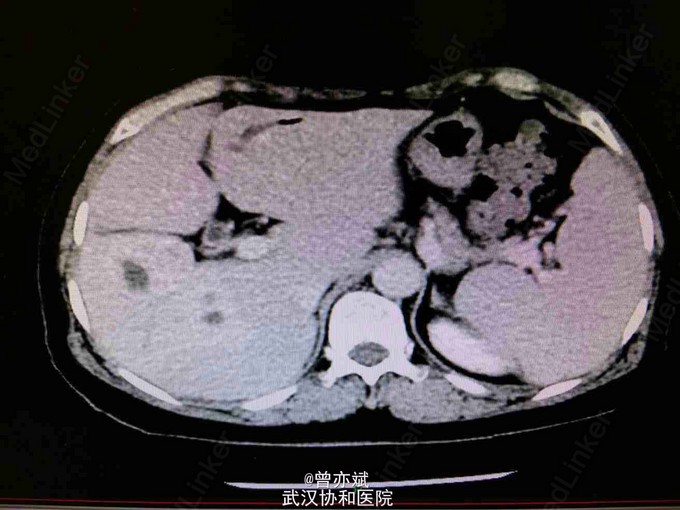

患者,女64岁,“发热两周”,患者两周前无明显诱因出现发热,体温最高达40摄氏度,伴畏寒寒战,发热无明显规律。发热时伴头痛,热退后头痛缓解。伴干咳无痰,伴乏力,恶心,呕吐为胃内容物。伴腰痛腹胀,无尿频尿急腹泻。于当地医院行抗感染治疗(头孢哌酮,左氧氟沙星),仍持续发热。入院完善相关检查,腹部增强CT如图示,多患者,女64岁,“发热两周”,患者两周前无明显诱因出现发热,体温最高达40摄氏度,伴畏寒寒战,发热无明显规律。发热时伴头痛,热退后头痛缓解。伴干咳无痰,伴乏力,恶心,呕吐为胃内容物。伴腰痛腹胀,无尿频尿急腹泻。于当地医院行抗感染治疗(头孢哌酮,左氧氟沙星),仍持续发热。入院完善相关检查,腹部增强CT如图示,多考虑肝脓肿,拟外科手术治疗。